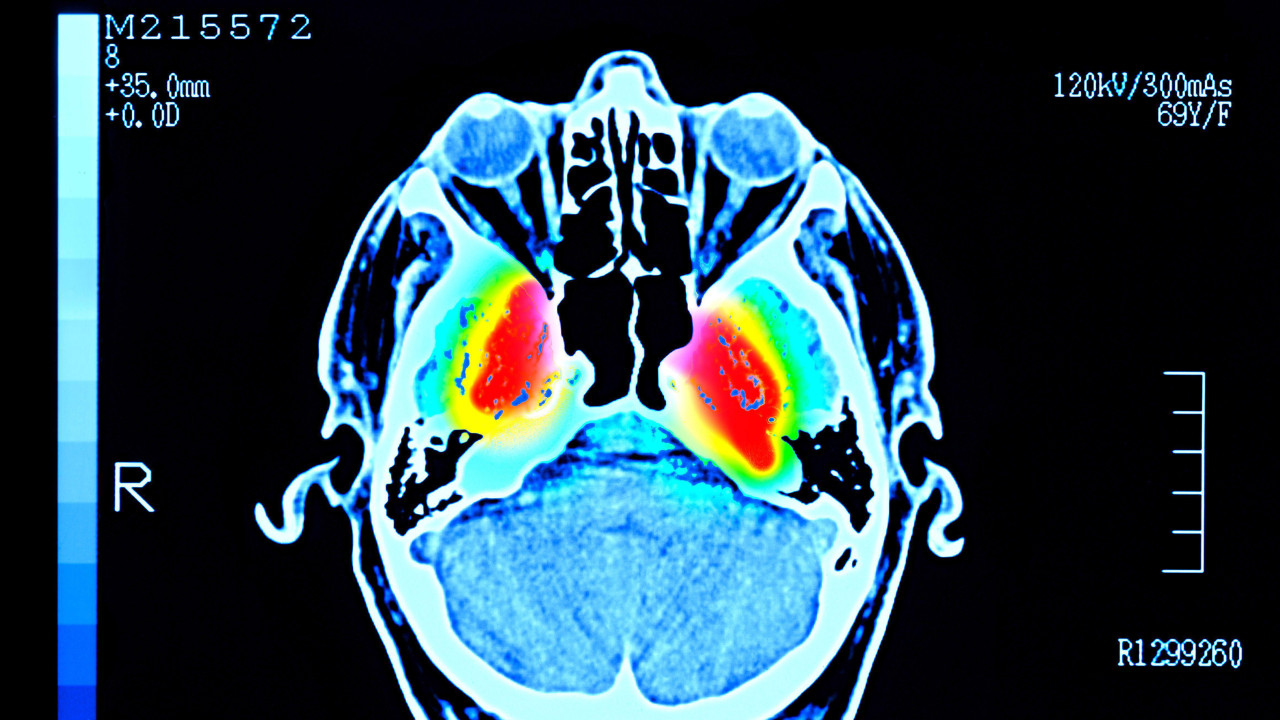

Istraživači su analizirali snimke mozga oko 4.000 ljudi starosti do 90 godina da bi otkrili obrasce veza između njihovih moždanih ćelija.